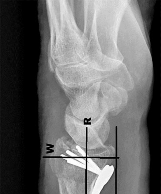

Question 20:

A 58-year-old male with long-standing, poorly controlled diabetes presents with a unilaterally swollen, warm, and erythematous foot without ulceration. Radiographs reveal osseous fragmentation, debris, and joint subluxation in the midfoot, but no significant sclerosis or osteophyte formation. According to the Eichenholtz classification of Charcot neuroarthropathy, what stage does this represent?

Correct Answer: Stage 1 (Development/Fragmentation)

Explanation:

The Eichenholtz classification describes the radiographic progression of Charcot neuroarthropathy. Stage 0 is clinically swollen and warm with normal radiographs. Stage 1 (Development/Fragmentation) features bony debris, fragmentation, joint subluxation/dislocation, and loss of joint space. Stage 2 (Coalescence) is marked by absorption of fine debris, early fusion of fragments, and sclerosis. Stage 3 (Reconstruction) shows consolidation of fractures, remodeling, and mature osteophyte formation.